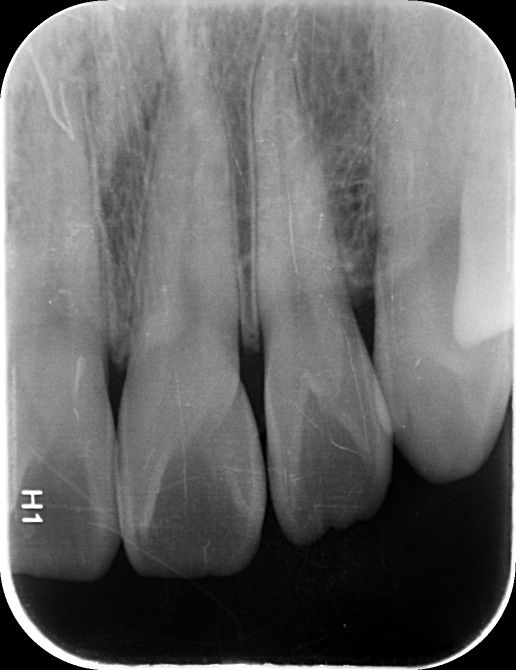

안녕하세요! 최근에 건강보험검진을 받으러가서 앞니 사이에 충치가 의심된다구 찍은 사진입니다.

1. 앞니에 충치가 있는건가요? (앞니 12, 11, 21, 22번 사이가 의심된다구 하셨습니다.)

2. 충치가 있다면 어디에 있는건가요? (치아번호로 말씀해주시면 감사하겠습니다!)

3. 치료를 받을정도의 충치인가요? 아니면 앞으로 관리를 통해 지켜보는게 좋을까요?

엑스레이 사진상으로 보면 치아 사이에 작은 충치가 잇는것처럼 보이긴합니다. #11 12 사이 21 22사이는 사진상으로 보이는데 #11 21 사이는 사진상에 겹쳐보여 직접봐야 알수 잇을것같습니다.